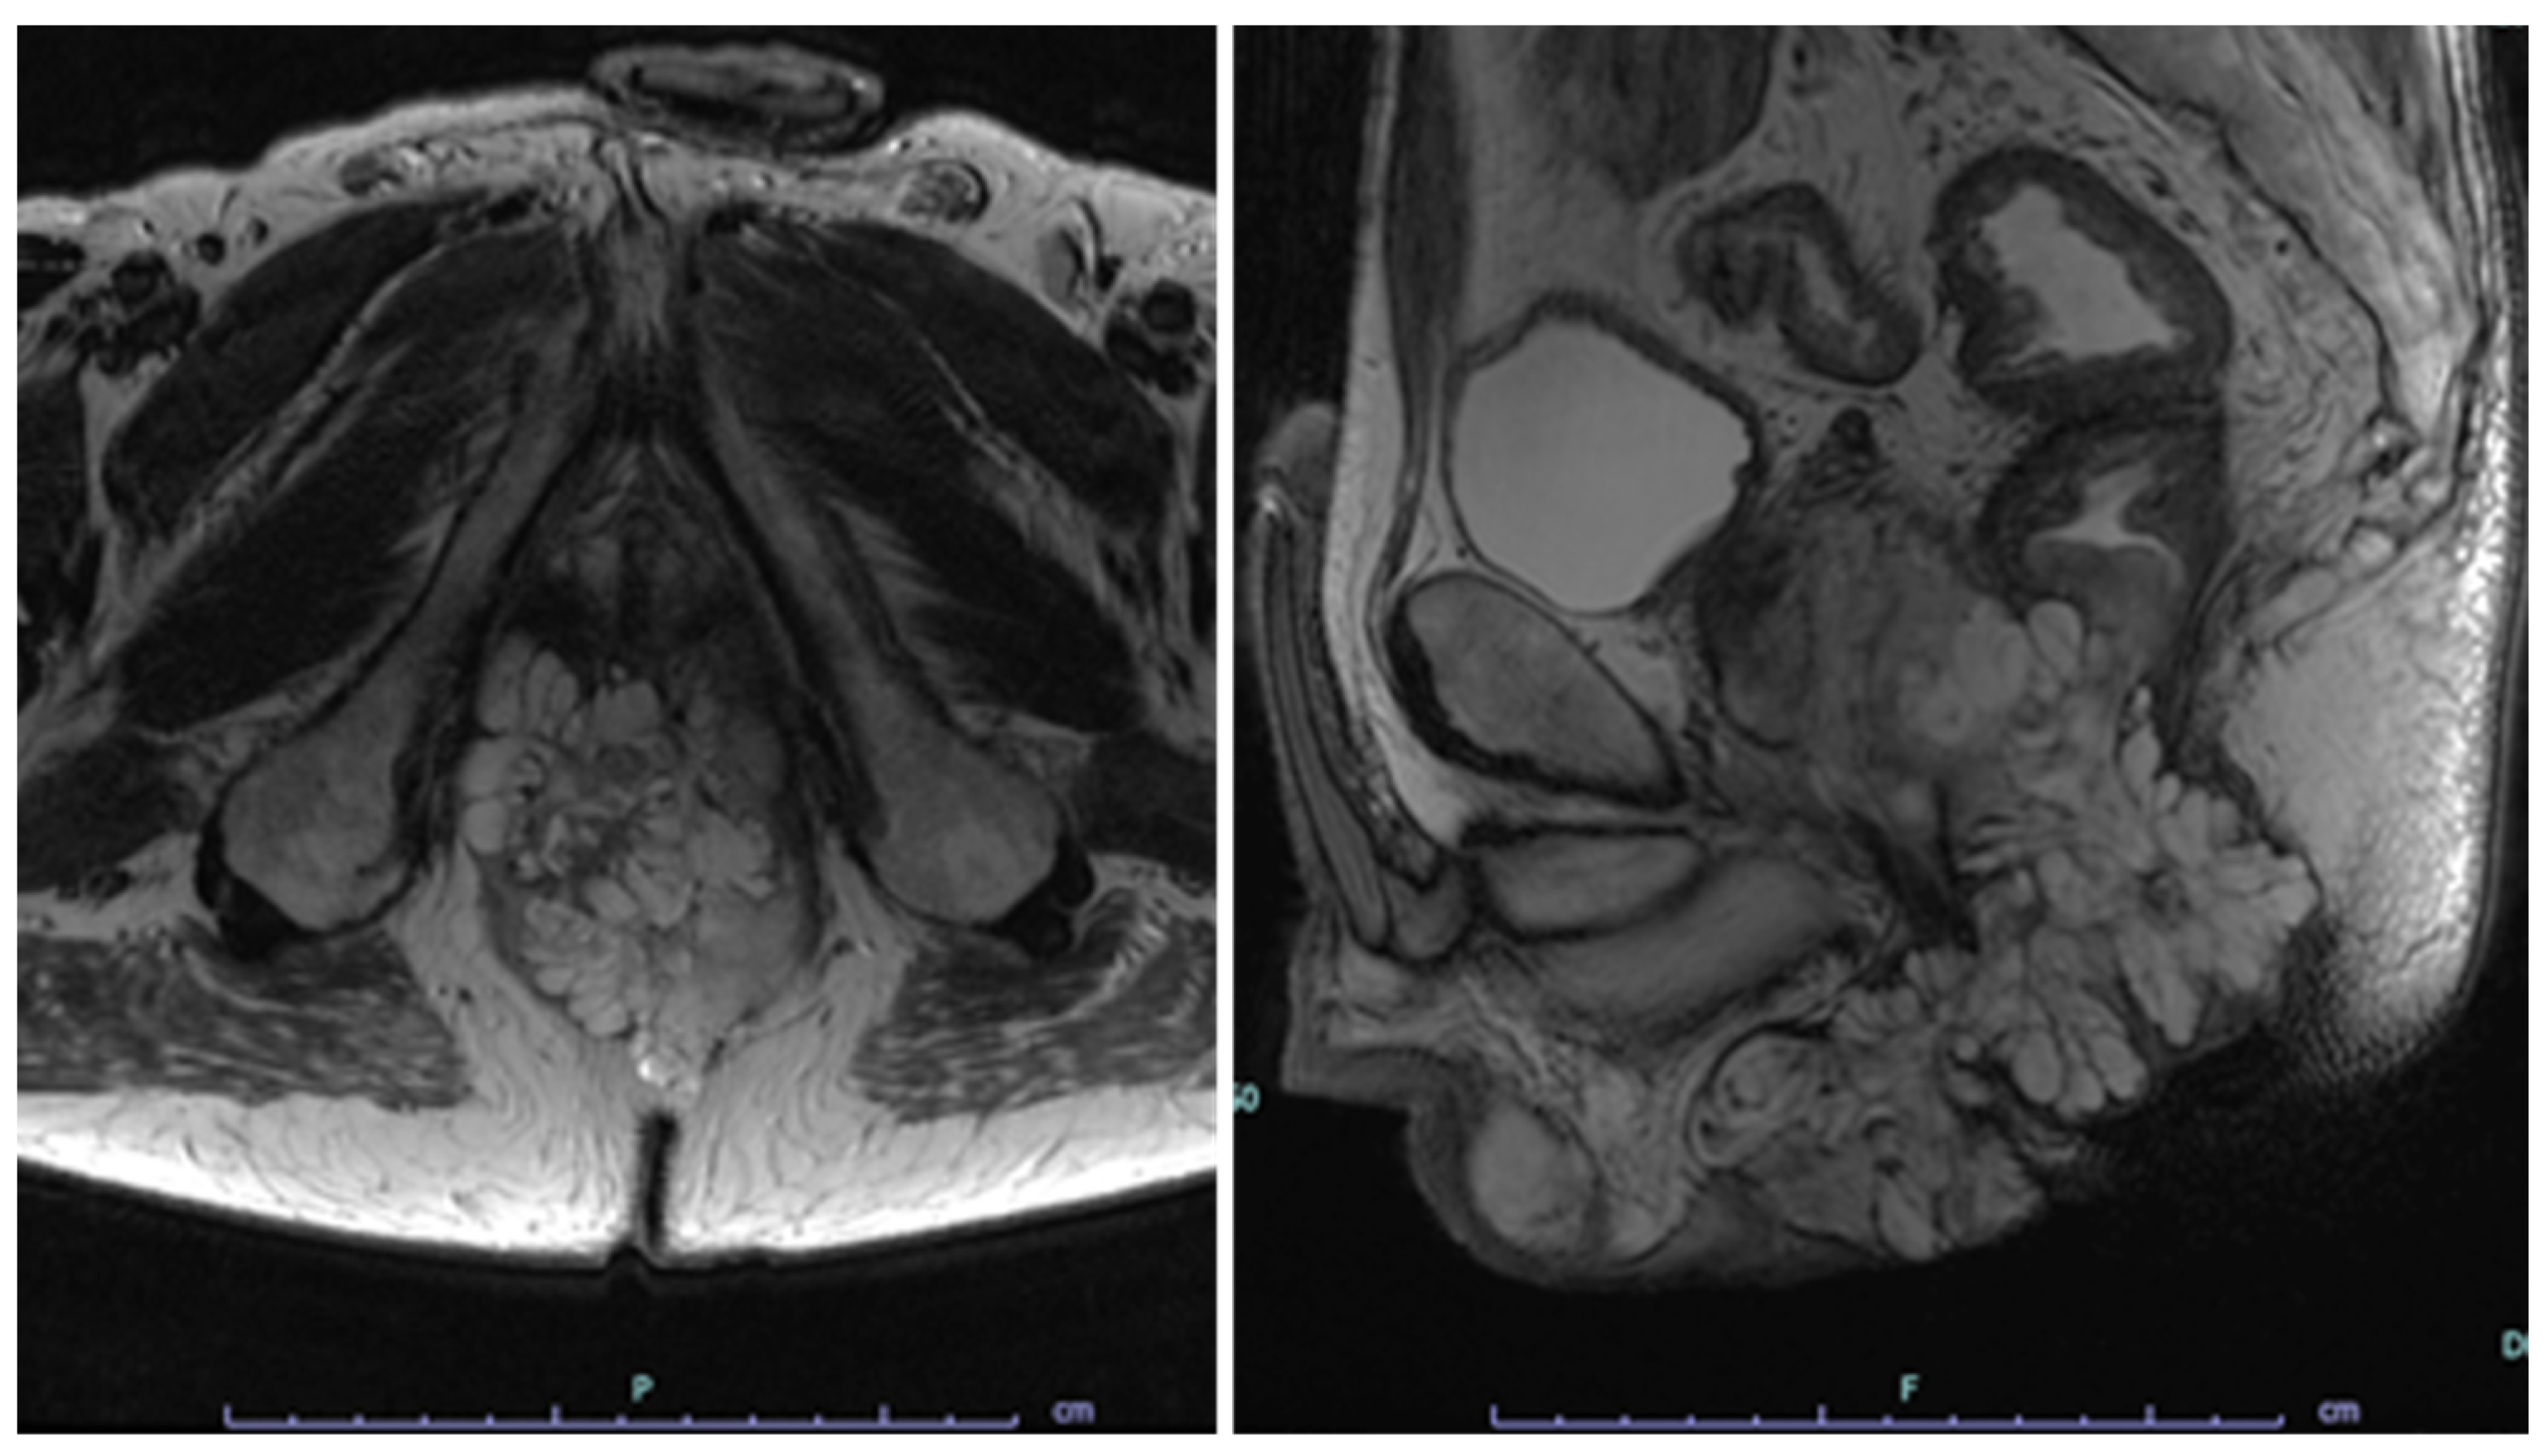

- Matsuno, H.; Mizushima, T.; Nezu, R.; Nakajima, K.; Takahashi, H.; Haraguchi, N.; Nishimura, J.; Hata, T.; Yamamoto, H.; Doki, Y.; et al. Detection of Anorectal Cancer among Patients with Crohn’s Disease Undergoing Surveillance with Various Biopsy Methods. Digestion 2016, 94, 24–29. [Google Scholar] [CrossRef]

- Hirano, Y.; Futami, K.; Higashi, D.; Mikami, K.; Maekawa, T. Anorectal cancer surveillance in Crohn’s disease. J. Anus Rectum Colon 2018, 2, 145–154. [Google Scholar] [CrossRef] [PubMed]